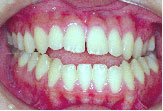

Before

下の歯が上の歯より前に出て前歯は咬めていません。左上の第2小臼歯は骨の中に埋まっています。

また下あごは左にずれています。顎変形症、下顎前突と診断しました。